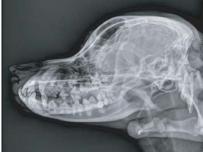

In recent veterinary practice, Digital Radiography (DR) is rapidly becoming the new standard to replace the traditional film-based x-ray technology. VXR is a Digital Radiography system based on CCD detector for Veterinary Hospital use. VXR is designed to provide customers with the high performance DR equipment at affordable price. VXR uses a very stable detector compared to CR and Flat panel detectors. Furthermore VXR provides high quality images for all diagnostic purposes.